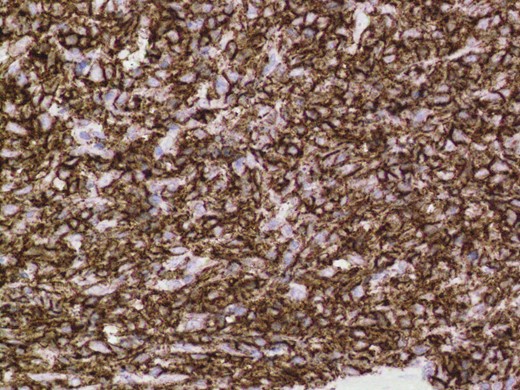

Given the high likelihood of significant vascular disease, a computed tomography (CT) angiogram was done (Fig. 1). Bilateral internal iliac artery stenosis was noted with complete occlusion of the inferior mesenteric artery and right internal iliac artery. A positron emission tomography (PET) scan showed only localized disease (Fig. 2). Magnetic resonance imaging (MRI) of his pelvis was significant for a large posterior abscess cavity with soft tissue at the margins with a cavity tracking superiorly along the posterior rectal plane (Fig. 3). The internal sphincter was noted to be necrotic on the last examination (Fig. 4) with a horseshoe cavity and a 10-cm tract running up the posterior aspect of the rectum. Multiple biopsies were taken from the anal margin, abscess cavity and peri-anal tissue, and the histology was consistent with diffuse large B-cell lymphoma. There were sheets of large atypical lymphocytes with extensive areas of necrosis. The tumour cells showed strong and diffuse immunohistochemical reactivity for CD20 (Fig. 5), indicating B-cell differentiation. The Ki67 proliferation index was very high (>90%) (Fig. 6) and there was positive in situ hybridisation (ISH) for Epstein-Barr virus (EBV) (Fig. 7). Fluorescence in situ hybridisation (FISH) was performed using a MYC dual colour break apart probe (8q24), and no rearrangement of the MYC gene region was detected. The combined morphological and FISH features were not considered to be those of Burkitt lymphoma.

Positive immuno-histochemistry for CD20 indicates a B cell lymphoma.